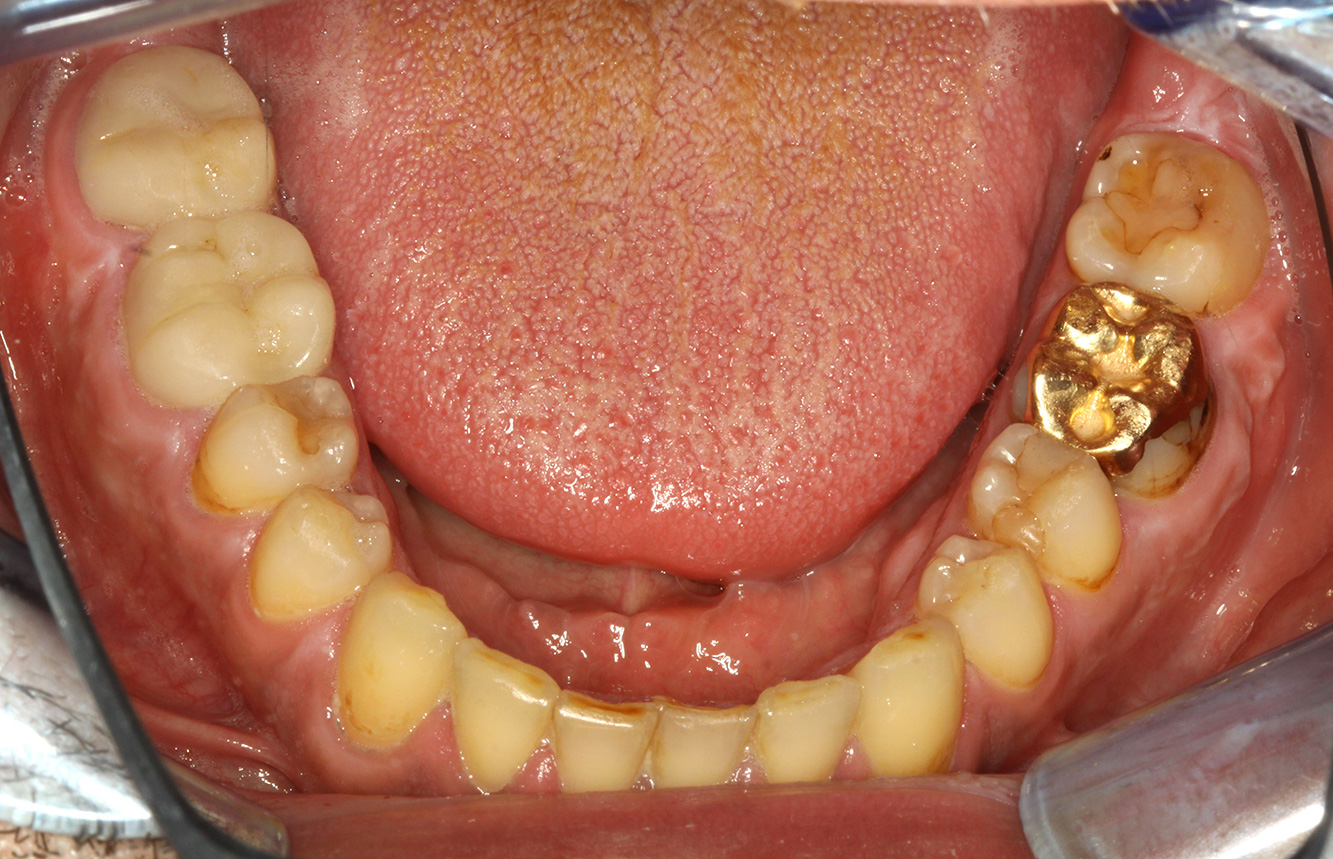

El paciente tiene 39 años con valvuloplastia frente a una insuficiencia valvular y endocarditis. Toma regularmente ASS 100 (ácido acetil salicílico) como anticoagulante. En el ámbito del estilo de vida, la alimentación se identifica como promotora de caries, ya que suele consumir alimentos azucarados y seis o siete comidas al día. La salud oral del paciente muestra un riesgo medio de caries con lesiones activas. El riesgo de periodontitis es bajo, presenta gingivitis. Se hacen las siguientes recomendaciones para el tratamiento profiláctico.

Para la sesión de profilaxis no hay recomendaciones específicas de instrumental. Mediante el uso dirigido de un aeropulidor y del pulido rotativo, puede eliminarse suavemente la placa y la decoloración en los bordes de la restauración y reducirse los nichos de recolonización para bacterias carcinógenas (19).